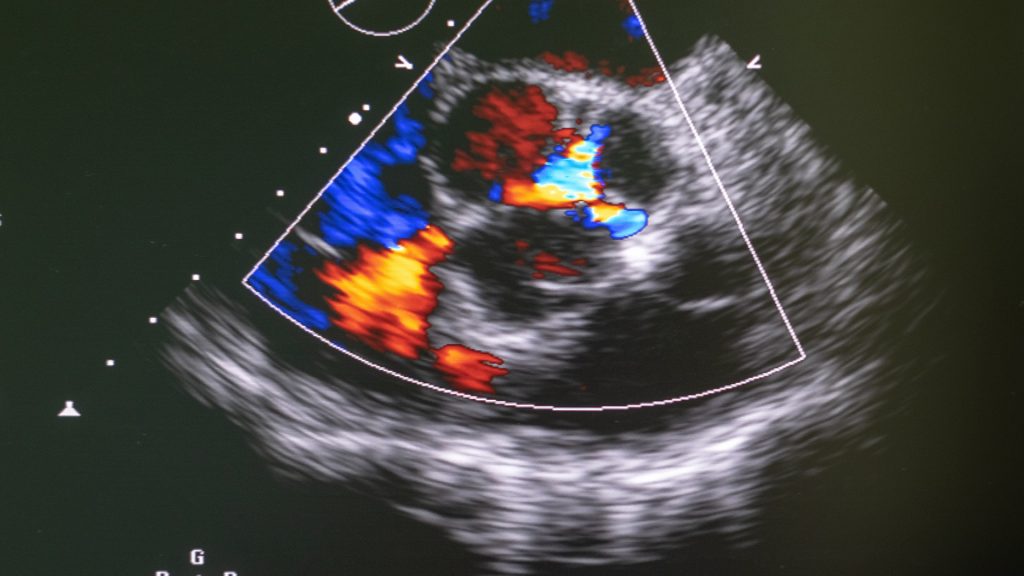

Ovaj pregled koristi kolor dopler ultrazvuk za analizu krvnih sudova (arterija i vena) u različitim delovima tela, uključujući vrat, ruke, noge i trbušnu aortu. Ova savremena, brza i bezbolna metoda pomaže u otkrivanju:

– Bolesti vena kao što su venska tromboza (krvni ugrušci u venama) i venska insuficijencija (loša cirkulacija u venama)

– Bolesti arterija kao što su ateroskleroza (suženje arterija), karotidna bolest (glavni uzrok moždanog udara) i bolesti perifernih arterija u rukama i nogama, koje mogu dovesti do ozbiljnih komplikacija kao što je gangrena.